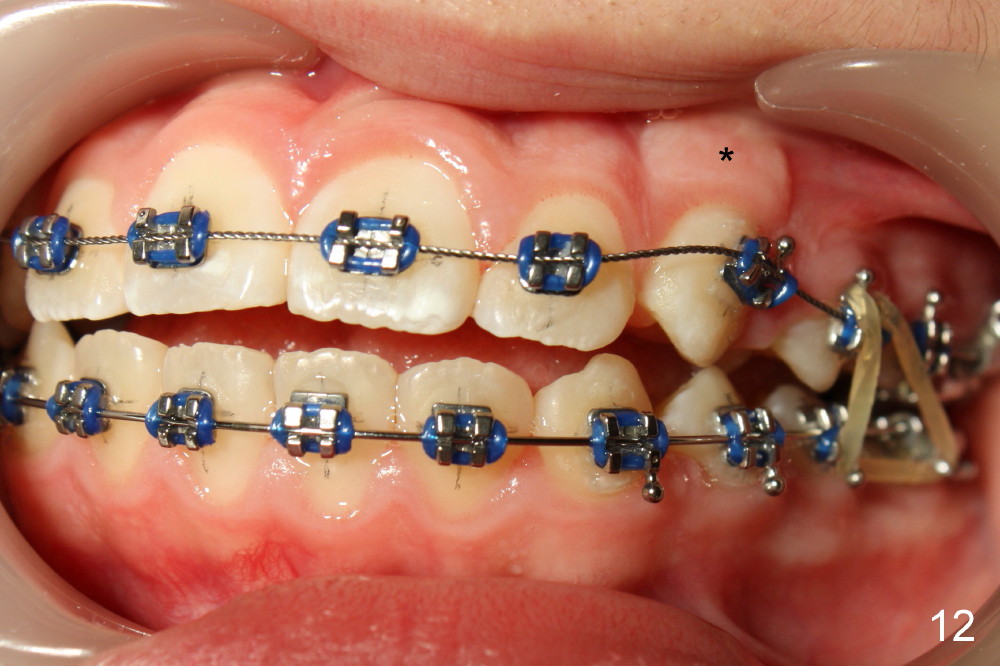

The canines are continually erupting 3 months of elastics (Fig.11,12). A flexible wire (.0175' twisted wire) is installed for the upper arch for further orthodontically-assisted eruption (Fig.12).

One month later, the canines has erupted completely at the expense of aggravation of anterior open bite (Fig.13,14, compare to Fig.11,12). Elastics are placed between the upper and lower incisors (Fig.14) following placement of .016' stainless steel wire for the upper arch (Fig.13).